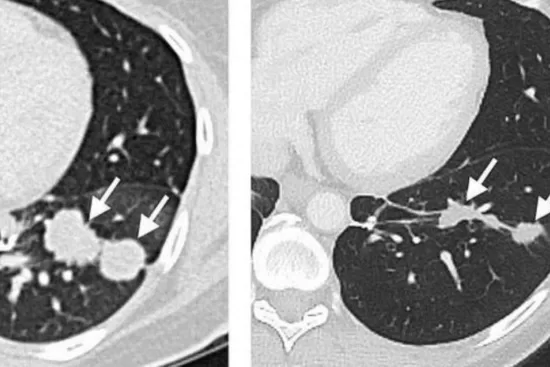

La inmunoterapia es un campo amplio, con opciones que van desde terapias con células CAR-T hasta inhibidores de puntos de control inmunológico. Oncovix se destaca en este panorama con su avanzada inmunoterapia basada en Exosomas de Células Dendríticas Pulsadas, una biotecnología de alta adaptabilidad aplicable a cualquier tipo de cáncer. Esta versatilidad permite que todos los pacientes puedan acceder al tratamiento, eliminando las limitaciones de selección y adaptándose a las necesidades específicas de cada caso.

Oncovix ha logrado revolucionar el acceso a la inmunoterapia de precisión al personalizar cada tratamiento según el perfil genético y/o molecular del tumor, lo que aumenta significativamente su eficacia. Además, al aprovechar los últimos avances en biotecnología, Oncovix ha registrado numerosos casos de éxito en colaboración con la red OCC Red Cáncer y el consorcio OGRD, documentando progresos incluso hacia la erradicación del cáncer o remisión total.